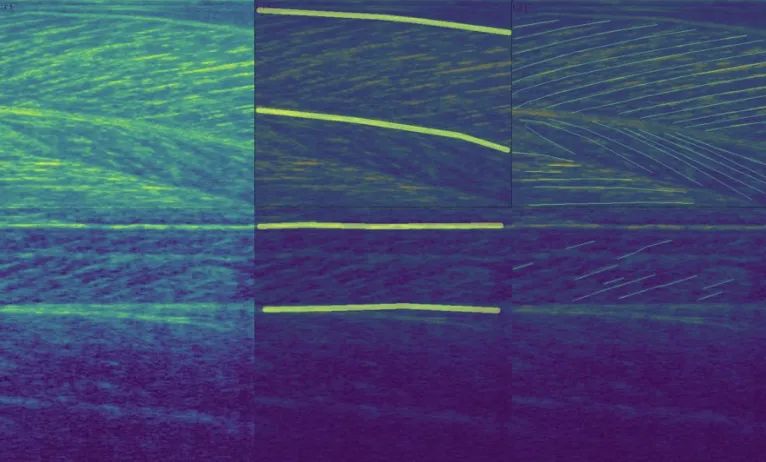

FASCICLE 小腿肌肉超声数据集

数据集链接:http://m6z.cn/631rex

FAscicle 小腿肌肉超声数据集是一个由 812 幅小腿肌肉超声图像组成的数据集,用于分析肌肉弱点并预防受伤。该数据集在文章 AW-Net:B 型超声图像上的自动肌肉结构分析以预防伤害中进行了介绍。它结合了由 Ryan Cunningham 等人发表的两篇文章“使用卷积、残差和反卷积神经网络从 B 模式超声图像中估计全区域骨骼肌纤维方向”提供的数据集。和 Neil Cronin 发表的“使用深度学习对肌肉骨骼超声图像进行自动分析”,并附有补充注释。

该 zip 文件包含两个数据集,分别分为两个由其作者命名的文件夹。每个数据集的每个图像都有一个匹配的分束分割掩码和一个可按名称识别的腱膜分割掩码。